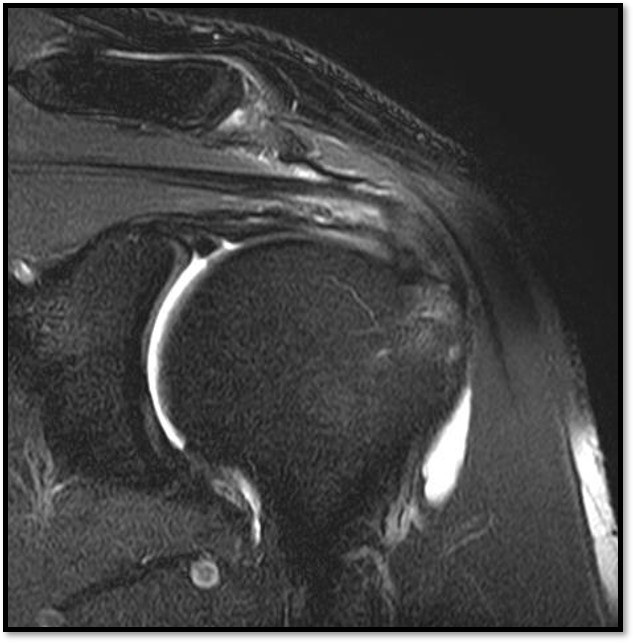

케이스 3: 소형 파열 + 젊은 환자 → 골수자극재생술

환자: 32세 남성, 크로스핏

진단:

MRI: 극상건 부분파열 (약 25%)

파열 양상: 가로 파열, 경미

치료:

골수자극재생술 (미세천공)

4세대 재생주사 병행

미세전류치료

결과:

10주 후 초음파: 파열 부위 재생 확인

4개월 후 크로스핏 복귀 (단, 강도 조절)